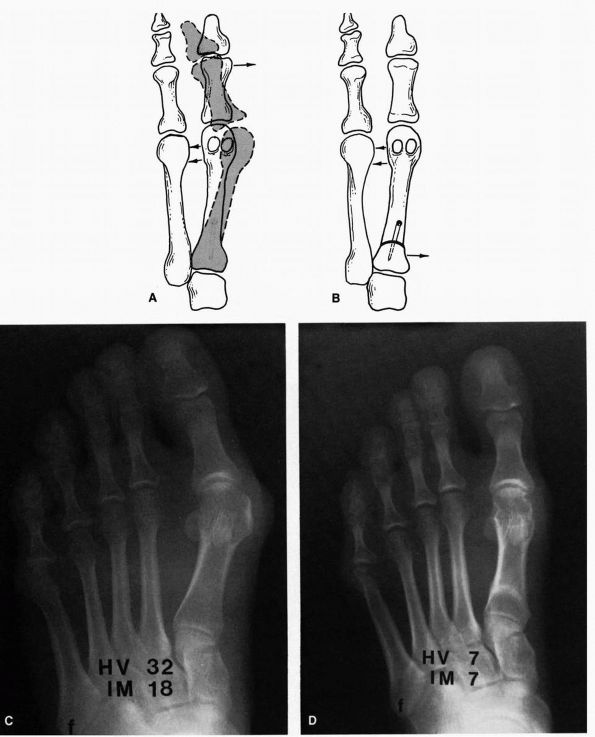

![]() |

FIGURE 21-5. Chevron procedure. (A) The apex of the chevron osteotomy starts in the center of the metatarsal head and is brought proximally. (B) The osteotomy site is displaced laterally 20 to 30% of the width of the shaft. Preoperative (C) and postoperative (D)

radiographs demonstrating the Chevron osteotomy. (Mann RA, Coughlin MJ. The Video Textbook of Foot and Ankle Surgery. St Louis: Medical Video Productions, 1991) |

deviation of the joint surface may result in creating an incongruent

joint out of a congruent one, resulting in stiffness and arthritis. The

angle between the joint surface and the metatarsal shaft can be

corrected by means of a closing-wedge modification of the Chevron

osteotomy. More severe cases require the addition of a proximal

procedure as well.